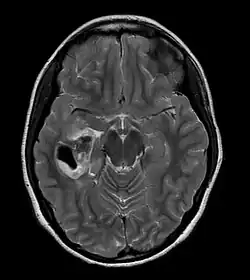

| CT scan of a brain with pleomorphic xanthoastrocytoma. The classic radiographic appearance is one of a superficially situated tumor, here a mural nodule, associated with an underlying cyst. |

- A CT scan of the brain, and/or an MRI scan of the brain and spine, will be performed. A special dye may be injected into a vein before these scans to provide contrast and make tumors easier to see.